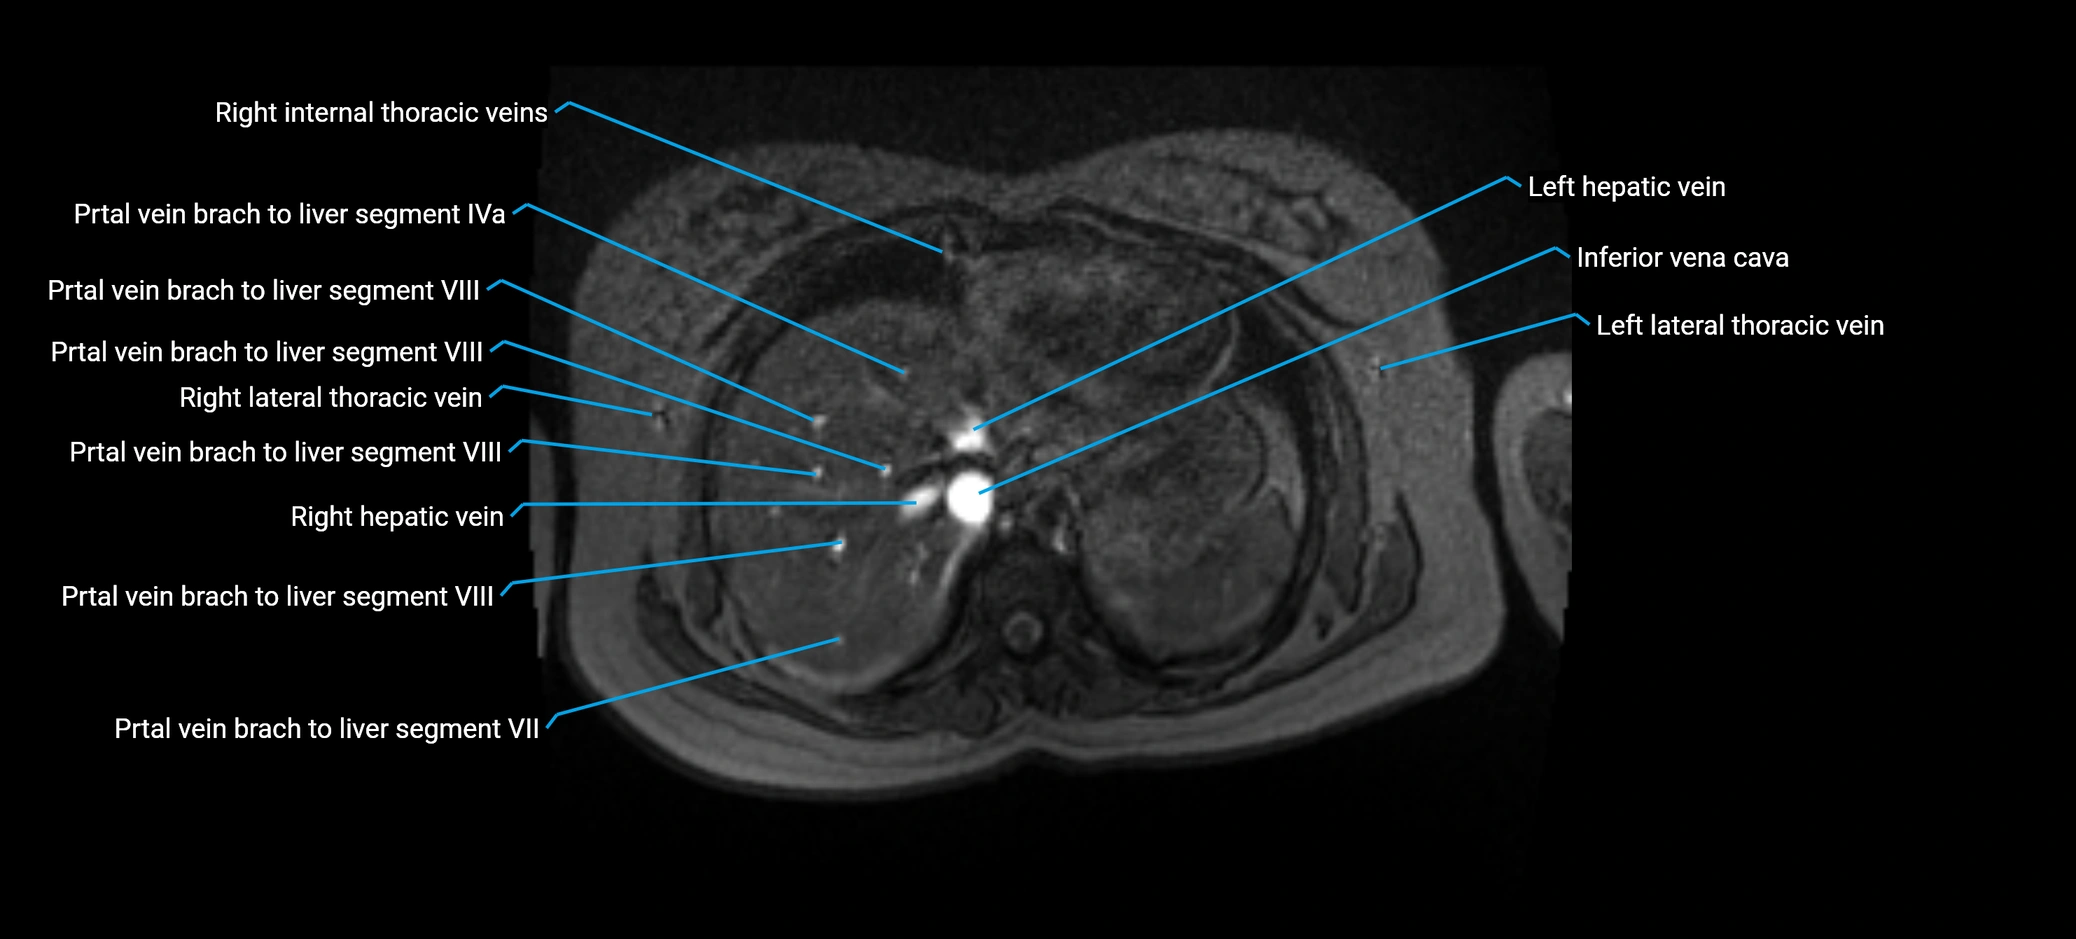

MRI image

image